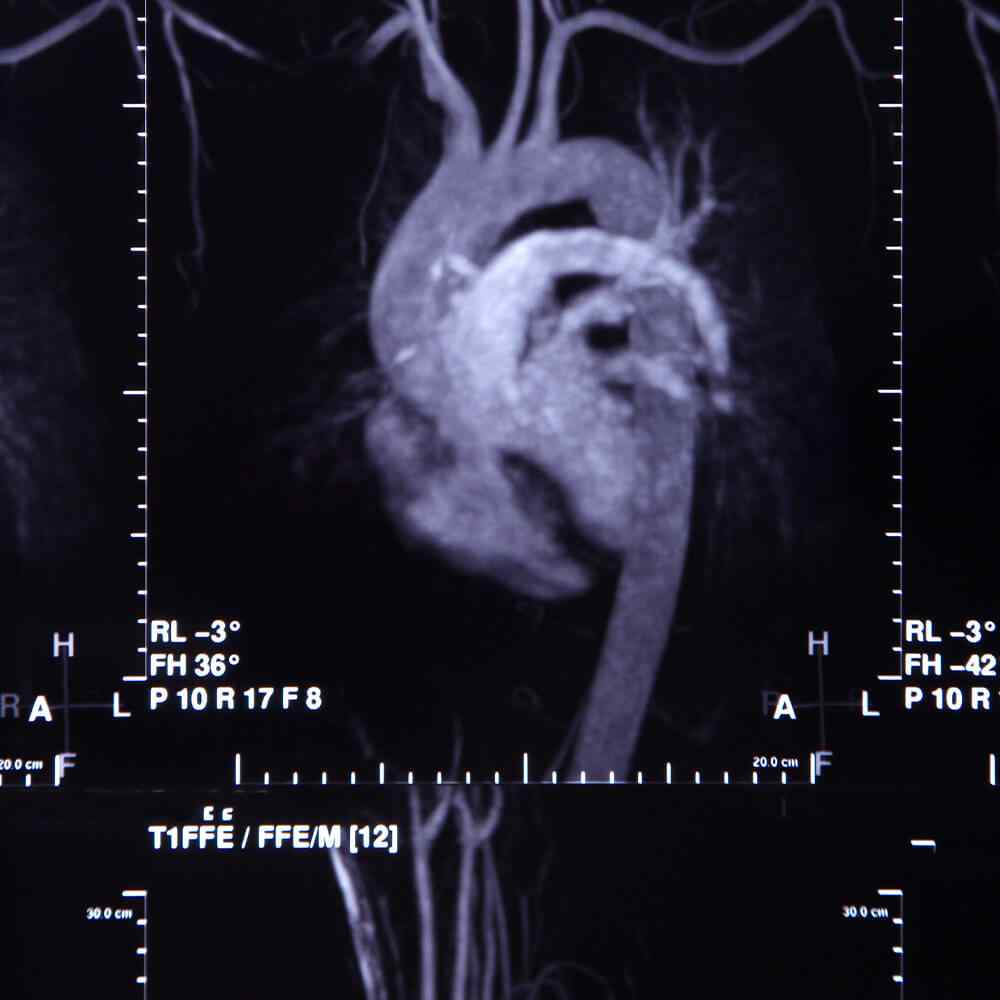

Atherosclerosis is thickening or hardening of the arteries caused by a buildup of plaque in the inner lining of an artery. Can cause a heart attack, stroke, aneurysm, or blood clot.

Atherosclerosis is the buildup of fats, cholesterol and other substances in and on your artery walls. This buildup is called plaque. The plaque can cause your arteries to narrow, blocking blood flow. The plaque can also burst, leading to a blood clot.